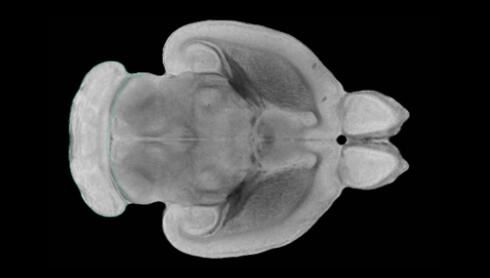

近日,一項(xiàng)刊登在國(guó)際雜志Nature上的研究報(bào)告中,來(lái)自劍橋大學(xué)的科學(xué)家們通過(guò)研究揭示了隨著年齡增長(zhǎng)大腦僵硬程度的增加導(dǎo)致大腦干細(xì)胞功能異常的分子機(jī)制,同時(shí)研究者還開(kāi)發(fā)出了一種新方法能將老化的干細(xì)胞逆轉(zhuǎn)回年齡健康狀態(tài);相關(guān)研究結(jié)果有望幫助研究人員理解機(jī)體大腦的老化過(guò)程以及如何開(kāi)發(fā)治療年齡相關(guān)大腦疾病的新型療法。

隨著機(jī)體年齡增加,肌肉和關(guān)節(jié)都會(huì)變得僵硬,這就會(huì)使得日?;顒?dòng)變得更加困難,本文研究表明,我們的大腦也是如此,與年齡相關(guān)的大腦僵硬對(duì)大腦干細(xì)胞的功能或許有著重要影響。文章中,研究人員對(duì)年輕和老化大鼠的大腦進(jìn)行研究闡明了年齡相關(guān)大腦僵硬對(duì)少突膠質(zhì)前體細(xì)胞(OPCs,oligodendrocyte progenitor cells)功能的影響。OPCs是一類(lèi)對(duì)維持正常大腦功能非常重要的大腦干細(xì)胞,其對(duì)于髓磷脂的再生也非常重要,髓磷脂是神經(jīng)組織周?chē)闹厩?,在多發(fā)性硬化癥中髓磷脂的再生常常會(huì)被損傷,機(jī)體老化對(duì)這些細(xì)胞的影響常常會(huì)誘發(fā)多發(fā)性硬化癥的發(fā)生,這些細(xì)胞的功能在老化的健康人群中同樣會(huì)下降。

為了確定老化OPCs的功能缺失是否可以被逆轉(zhuǎn),研究人員將來(lái)自老化大鼠機(jī)體的老化OPCs轉(zhuǎn)移到了年輕大鼠柔軟的海綿狀大腦組織中去,值得注意的是,這些老化的大腦細(xì)胞能夠重新恢復(fù)活力,其行為非常像年輕更加強(qiáng)壯的細(xì)胞。這項(xiàng)研究中,研究人員在實(shí)驗(yàn)室中開(kāi)發(fā)出了具有可變僵硬程度的新型材料,并在受控環(huán)境下研究這些材料的生長(zhǎng)及其對(duì)大鼠大腦干細(xì)胞的影響,這些材料能被工程化改造具有和年齡或老化大腦相似的柔軟程度。